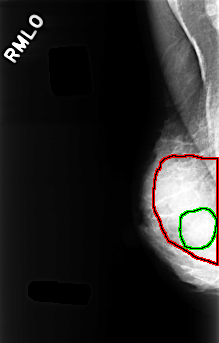

FILE: C_0329_1.RIGHT_MLO.OVERLAY

TOTAL_ABNORMALITIES 2

ABNORMALITY 1

LESION_TYPE CALCIFICATION TYPE PUNCTATE DISTRIBUTION DIFFUSELY_SCATTERED

ASSESSMENT 2

SUBTLETY 4

PATHOLOGY BENIGN

TOTAL_OUTLINES 1

BOUNDARY

ABNORMALITY 2

LESION_TYPE MASS SHAPE OVAL MARGINS OBSCURED

ASSESSMENT 3

SUBTLETY 3